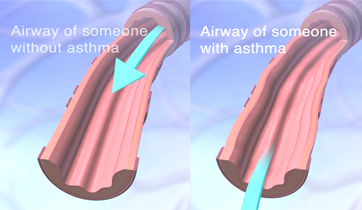

Asthma and its Triggers

Singulair, Merck

Rapp Collins Worldwide

New version in 2012 for UCSF

Patient education animation explaining Asthma and its triggers. The resulting constriction of the airways and the build up of mucus is explained, followed by tactics to maintain airflow and avoid attacks.